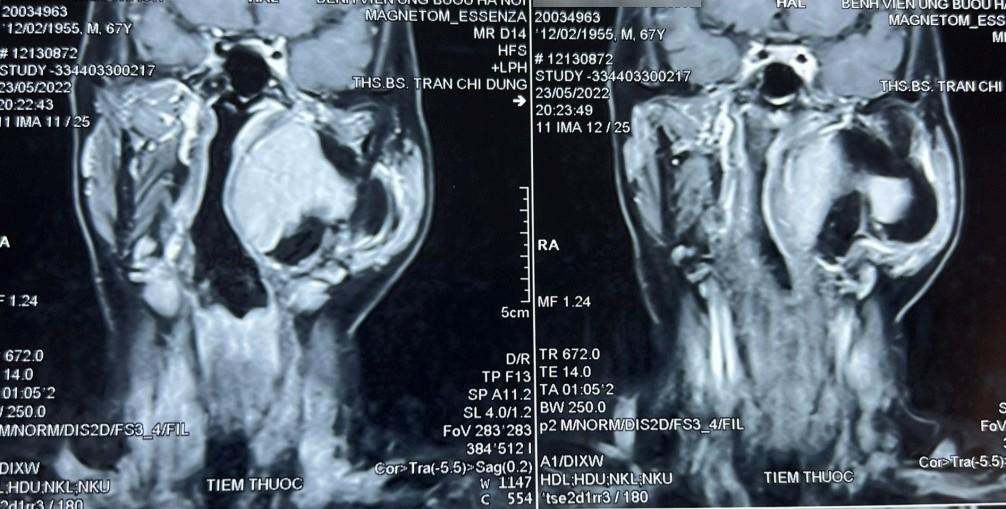

Bệnh nhân đến khám vì khối sưng phồng vùng mang tai trái, ngoài ra không kèm theo khó chịu gì. Qua thăm khám và đánh giá, bác sĩ phát hiện một khối u lớn vùng cổ kích thước khoảng 10 x 8 cm, thuộc khoảng bên họng, trải dài từ nền sọ xuống hạ họng, đẩy lệch thành bên họng vào trong, gồm 2 phần: phần nông nằm dưới tuyến mang tai và phần còn lại nằm sâu hơn.

Chẩn đoán sơ bộ ban đầu khối u là lành tính, ranh giới không rõ ràng. Thông qua hội chẩn các bác sĩ quyết định tiến hành phẫu thuật sớm lấy bỏ khối u tránh nguy cơ khối u chèn ép vào đường thở, đường ăn, thần kinh, mạch máu và các thành phần liên quan khác. Tiên lượng cuộc mổ là rất khó khăn, đường tiếp cận chính là qua mổ mở từ vùng cổ, phải thực hiện các thao tác phẫu thuật trong không gian hẹp, có thể kết hợp thêm hỗ trợ nội soi.